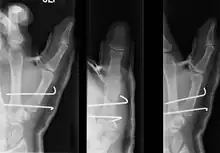

Bennett's fracture repair

• For Bennett fractures where there is between 1 mm and 3 mm of displacement at the trapeziometacarpal joint, closed reduction and percutaneous pin fixation (CRPP) with Kirschner wires is often sufficient to ensure a satisfactory functional outcome. The wires are not employed to connect the two fracture fragments together, but rather to secure the first or second metacarpal to the trapezium.

• For Bennett fractures where there is more than 3 mm of displacement at the trapeziometacarpal joint, open reduction and internal fixation (ORIF) is typically recommended.

Regardless of which approach is employed (nonsurgical, CRPP, or ORIF), immobilization in a cast or thumb spica splint is required for four to six weeks.